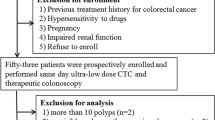

During the period of December 2023 to April 2024, a total of 110 consecutive patients who were scheduled to undergo CTC examination with clinically suspected CRC in our hospital were prospectively enrolled in this study. The exclusion criteria were as follows: patients with poor bowel preparation, unable to tolerate gas injection, metal artifacts from lumbar implants or total hip replacement, and patients who were recommended to use 120 kVp tube voltage by Auto prescription technique. Among the 110 patients, 11 patients who had no pathological report, 5 patients who had maximum tumor diameter less than 10 mm, and another 4 patients who underwent chemotherapy for treatment were further excluded from analysis. Thus, 90 patients finally made up of our study population (Fig. 1).